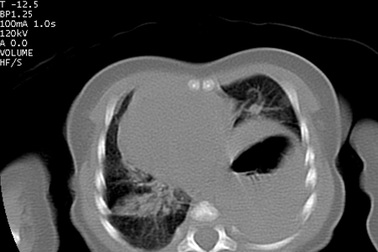

Bé trai 10 tháng tuổi có gan và quai ruột chui lên lồng ngựcMột bệnh nhi 10 tháng tuổi ở Thanh Hóa được phát hiện thoát vị hoành bên phải, cả gan phải và các quai ruột chui lên lồng ngực. Bệnh nhi được các bác sĩ phẫu thuật thành công và sức khỏe đã ổn định.

Bệnh nhi không thể chuyển viện, bác sĩ về tận nơi cứu sốngBị thoát vị hoành khiến nội tạng lộn lên lồng ngực, đẩy lệch tim sang phải, bé sơ sinh đối mặt với nguy cơ tử vong nhưng không thể chuyển viện an toàn. Trước tình huống khẩn nguy, các bác sĩ đã từ Sài Gòn về An Giang thực hiện nội soi giúp bé qua nguy kịch.

Hy hữu: Vỡ cơ hoành, đại tràng chui lên ngực vẫn tưởng hậu Covid-19Nam bệnh nhân 25 tuổi có tiền sử khỏe mạnh, vào viện khám vì nghĩ ho, khó thở hậu Covid-19. Tuy nhiên, nguyên nhân thực sự gây tình trạng này lại do bệnh nhân vỡ cơ hoành, tạng từ bụng chui lên ngực.